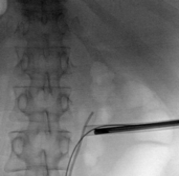

74-year-old male with a past medical history of nephrolithiasis, sleep apnea, thoracic aortic aneurysm, activated protein C resistance, Factor V deficiency, Gout, Hypertension and benign prostatic hyperplasia (BPH) presented for further evaluation regarding nephrolithiasis. The patient recently underwent extracorporeal shock wave lithotripsy (EWSL), and a post operative abdominal x-ray showed a calcification at the level of the right sacrum and a right ureteral stone could not be ruled out. A non-contrast CT abdomen and pelvis was ordered, which showed severe right hydroureteronephrosis due to two stacked distal right ureteral stones measuring 11 mm in size (Figure 3). Hounsfield units of the ureteral stones averaged 1895.

The patient underwent a right ureteroscopy and laser lithotripsy. Using a semi-rigid ureteroscope, a large impacted and obstructing stone was encountered. A hydrophilic wire was advanced past the stone into the renal pelvis. A ureteral catheter was advanced over the hydrophilic wire into the renal pelvis under fluoroscopic guidance, and the hydrophilic wire was exchanged for a super-stiff wire. Due to edema and tortuosity of the ureter, the semi rigid ureteroscope could not safely maintain visualization of the stone. Therefore, a 12/14 Fr x 28 cm ureteral access sheath was advanced to the level of the stone and a flexible ureteroscope was advanced to the level of the stone, to allow optimal visualization and laser lithotripsy.